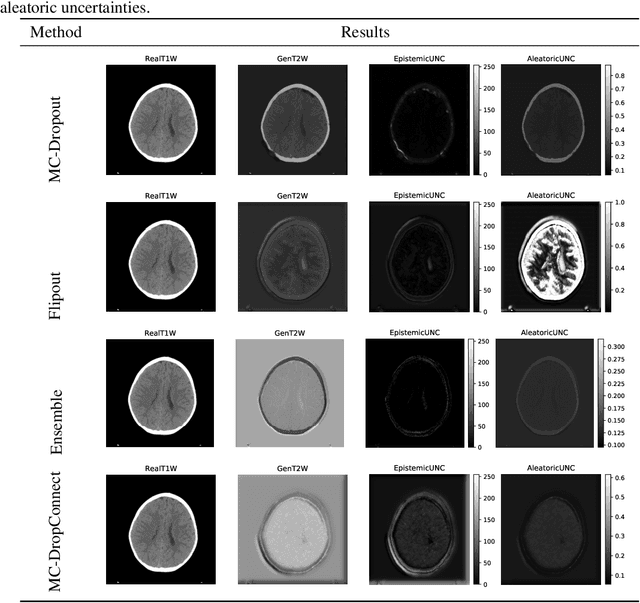

Abstract:Trusting the predictions of deep learning models in safety critical settings such as the medical domain is still not a viable option. Distentangled uncertainty quantification in the field of medical imaging has received little attention. In this paper, we study disentangled uncertainties in image to image translation tasks in the medical domain. We compare multiple uncertainty quantification methods, namely Ensembles, Flipout, Dropout, and DropConnect, while using CycleGAN to convert T1-weighted brain MRI scans to T2-weighted brain MRI scans. We further evaluate uncertainty behavior in the presence of out of distribution data (Brain CT and RGB Face Images), showing that epistemic uncertainty can be used to detect out of distribution inputs, which should increase reliability of model outputs.